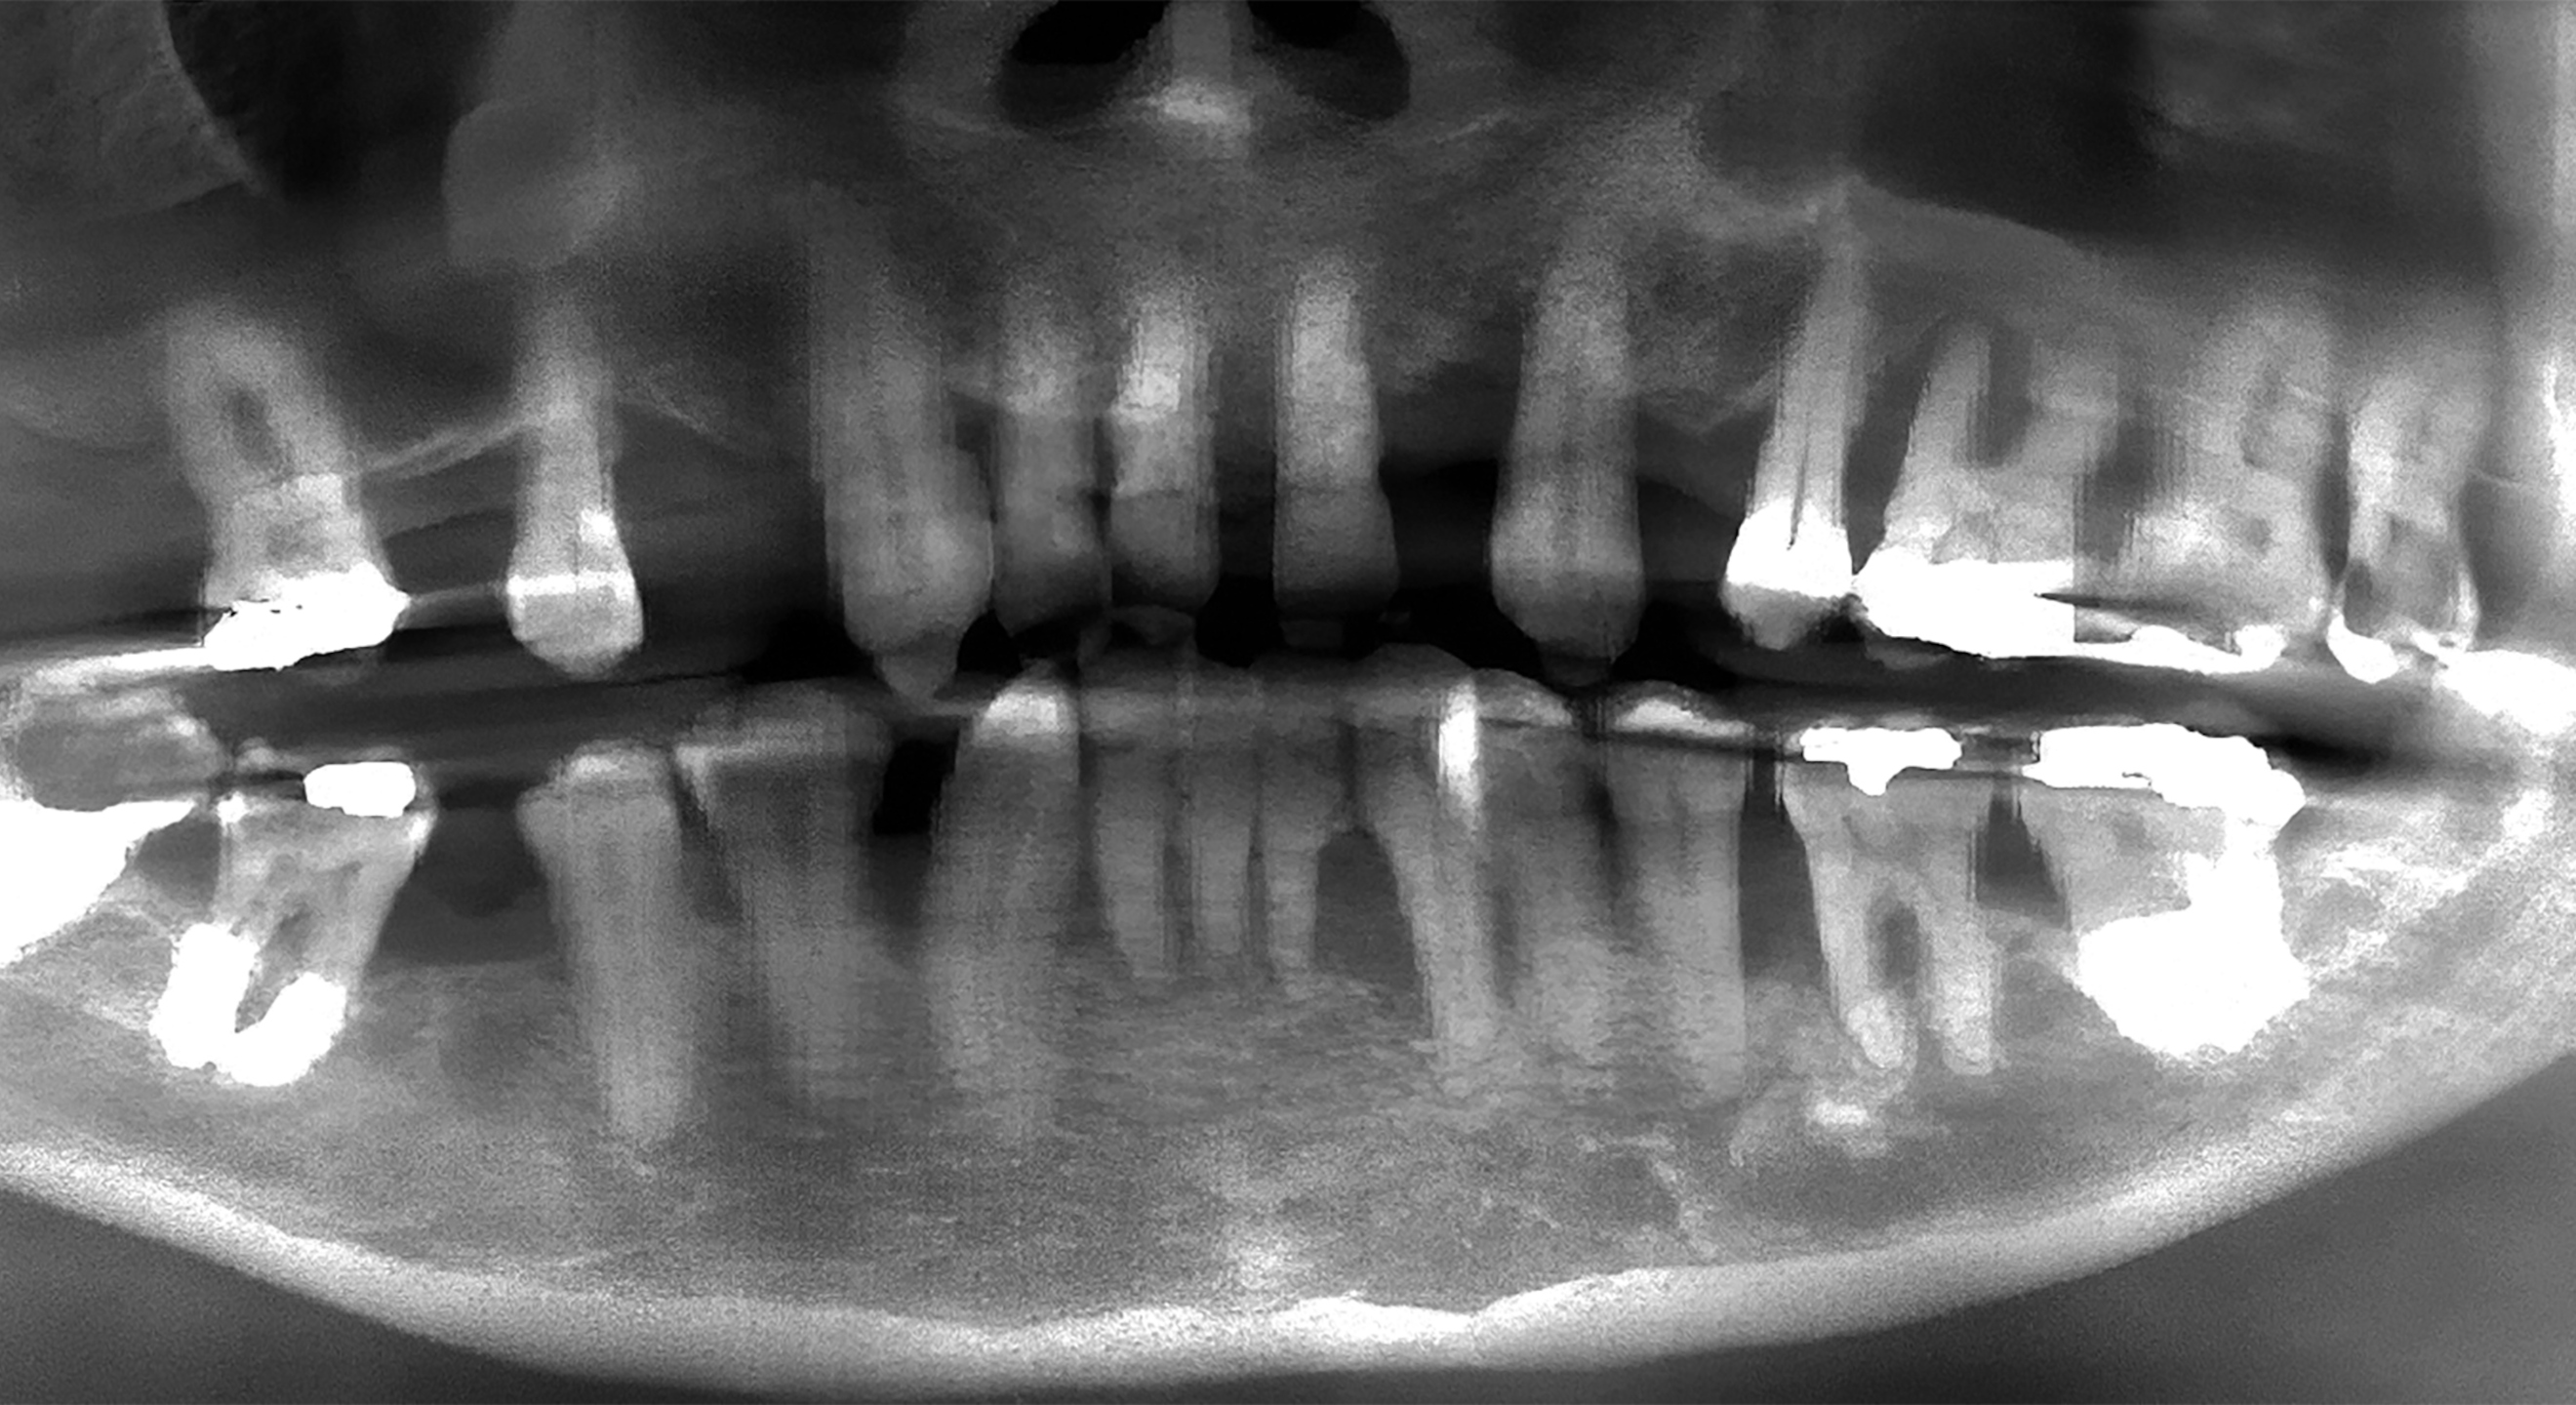

Fig. 1a: Pre-op situation. Intra-oral retracted view of the maxillary teeth, showing advanced periodontal disease and anterior spacing. (All images: Dr Scott D. Ganz)

A 49-year-old male patient presented with failing maxillary and mandibular teeth. The findings of the clinical and radiographic examinations were severe periodontal disease, generalised bone loss, anterior spacing and tooth mobility, in addition to overall poor hygiene maintenance (Figs. 1a & b & 2a). The patient was informed of the findings, and several treatment options were discussed, including complete and/or partial dentures, implant-supported overdentures and implant-supported fixed restorations. After discussion regarding the options, the patient decided on full-arch implant-supported fixed restorations.